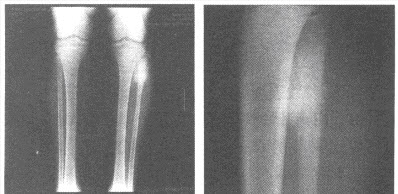

男,16岁,左小腿上端疼痛3个月余,局部肿胀,皮温稍高。结合左胫腓骨正侧位片,最可能的诊断为()

A:急性化脓性骨髓炎

B:骨化性肌炎

C:骨肉瘤

D:成软骨细胞瘤

E:软骨肉瘤